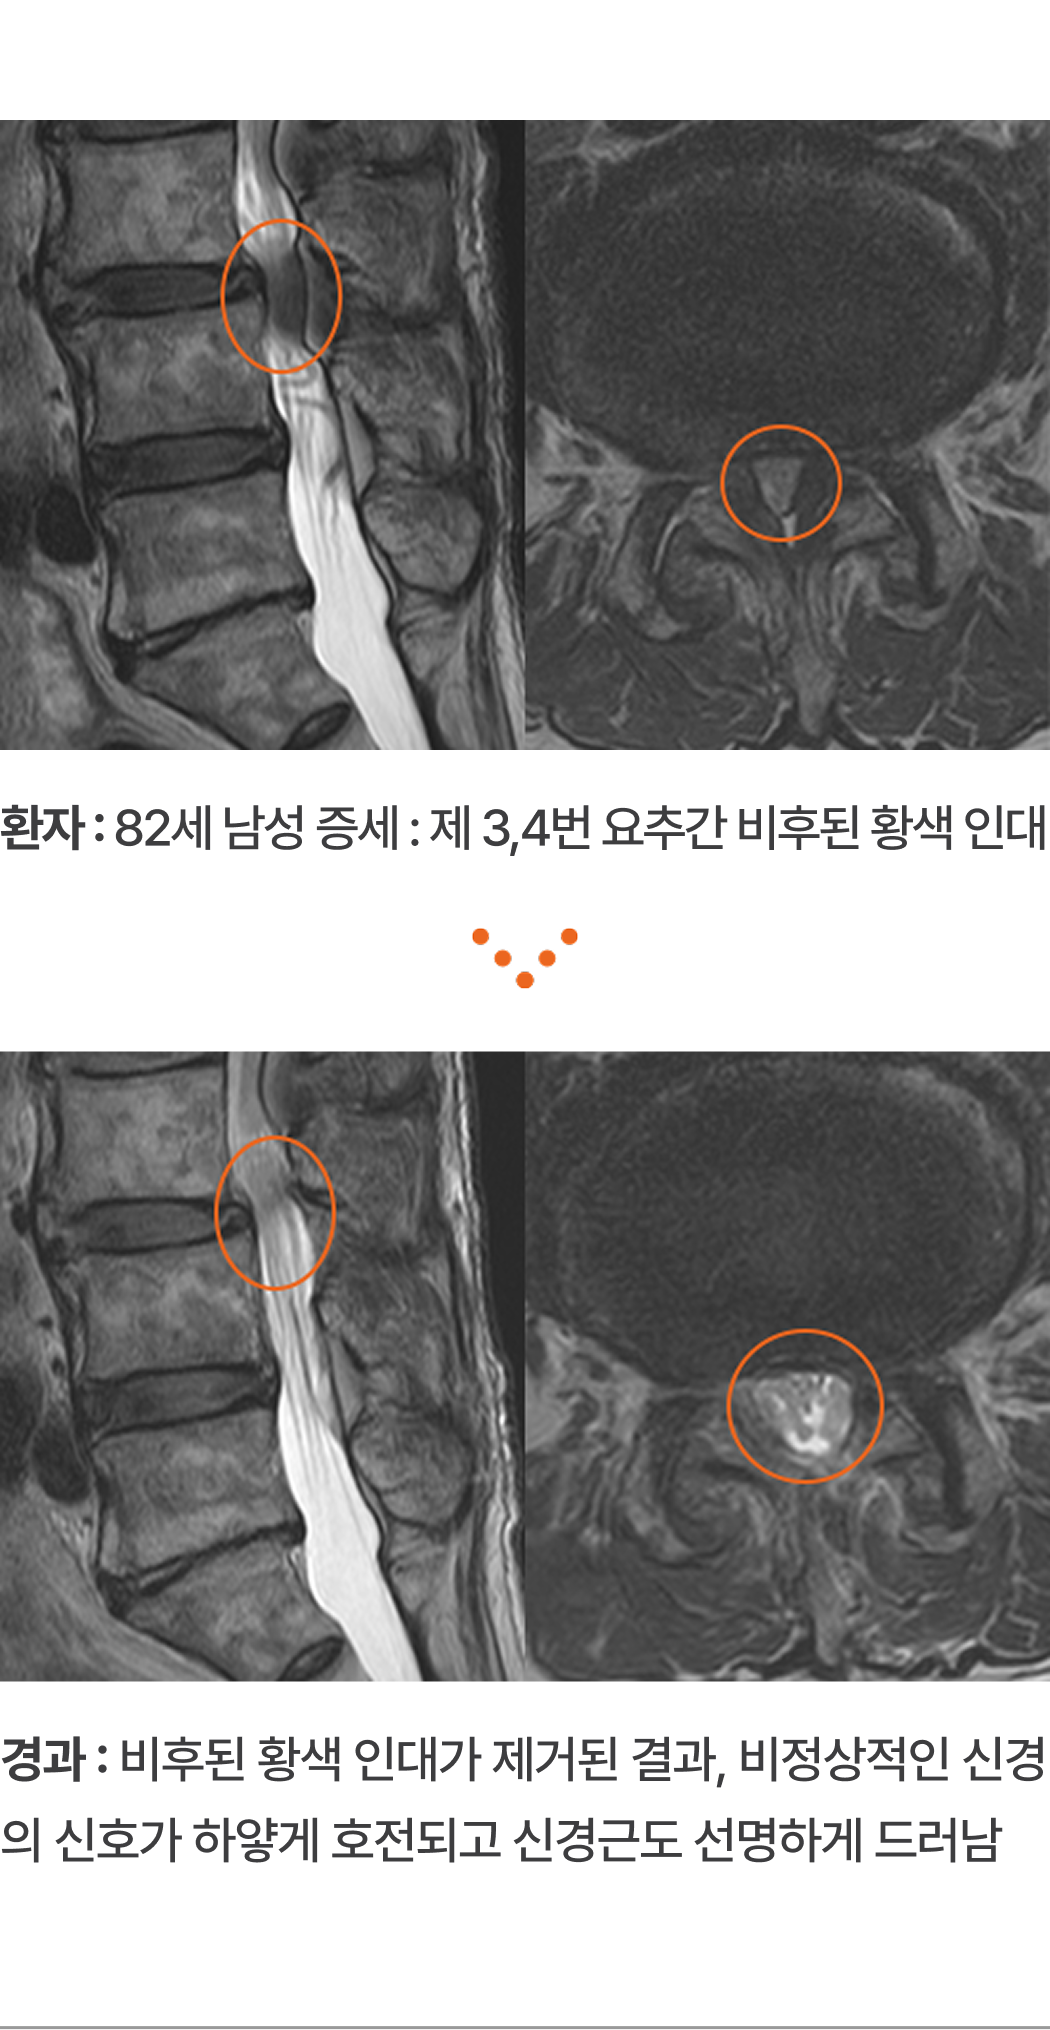

환자 : 82세 남성 증세 : 제 3,4번 요추간 비후된 황색 인대

경과 : 비후된 황색 인대가 제거된 결과, 비정상적인 신경의 신호가 하얗게 호전되고 신경근도 선명하게 드러남